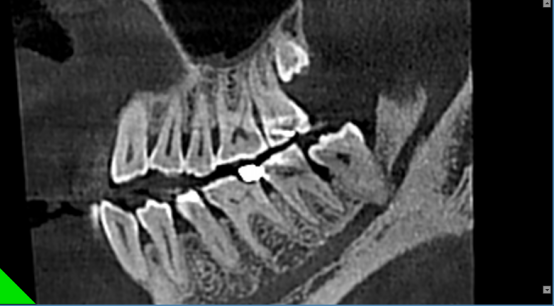

根管和牙周治疗过程中,提供牙根位置、角度、是否牙裂病变及下颌管、牙周围组织高清图像,以便于分辨治疗每个细节,做出精确诊断以及有效治疗方案。